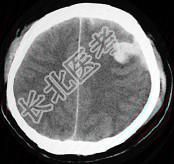

- 单项选择题女,52岁, 有高血压病史,半小时前突感头晕, 剧烈头痛,摔倒在自家楼下, CT检查如图所示,最可能的诊断是 ( )

E、脑出血